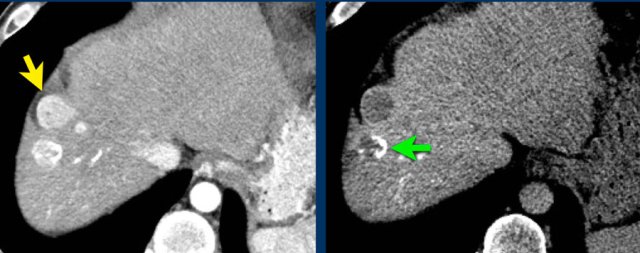

Here an image in the late arterial phase in a patient with cirrhosis.

There is an observation with non-rim hyperenhancement (yellow arrow).

In a late phase there is washout.

These are typical features of HCC.

The other lesion (green arrow) is a treated lesion, which we will discuss later.